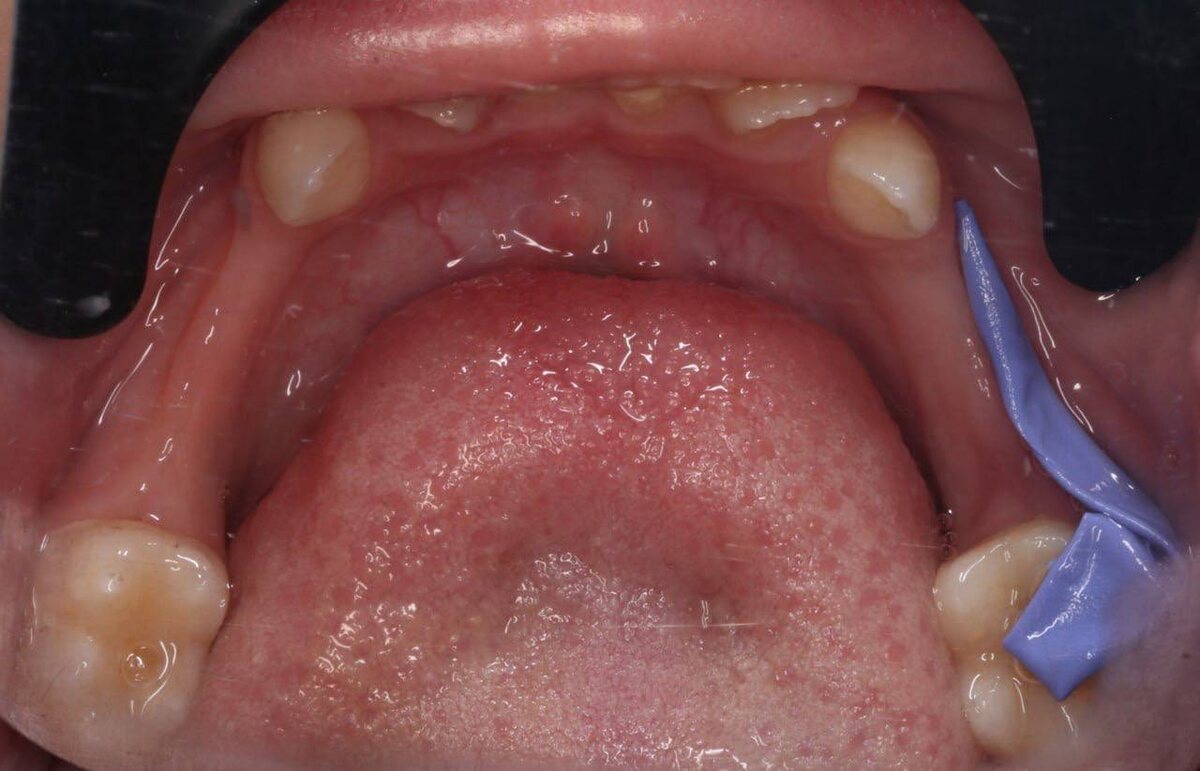

Состояние на момент обращения ⬇️

Ребёнок с сохраняющимся отёком, не может нормально открыть рот, не жуёт, плохо спит, принимает уже второй или третий антибиотик за короткий срок — без положительной динамики. Вся семья в состоянии сильного стресса.